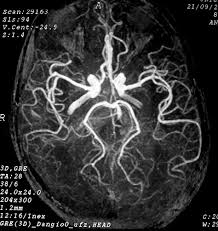

Mesmo com reperfusão angiográfica ‘bonita’, parte dos pacientes não melhora como esperado. D…

Ver mais

A trombectomia mudou o jogo nas oclusões de grandes vasos. Agora, o foco está se ampliando p…